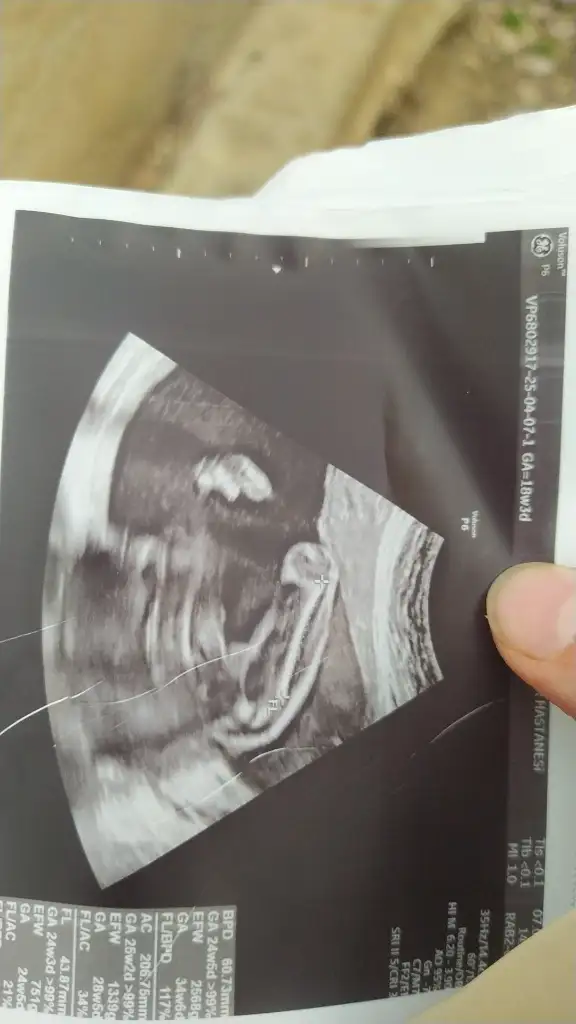

Sizce bu bebişin cinsiyeti nedirKuzum nub gözükmüyor tam o yüzden emin olmamakla birlikte benim kızıma benzettim kız diyim o yüzden

Bunada bakar mısınızErkek gibi

Bacak arasıysa erkek gibiBunada bakar mısınız

Evet bacak arası doktor yüzde 90 kız dedi yanlız bir cikintida var ama anlamadm diyorBacak arasıysa erkek gibi

Kordon'da olabilir canımEvet bacak arası doktor yüzde 90 kız dedi yanlız bir cikintida var ama anlamadm diyor